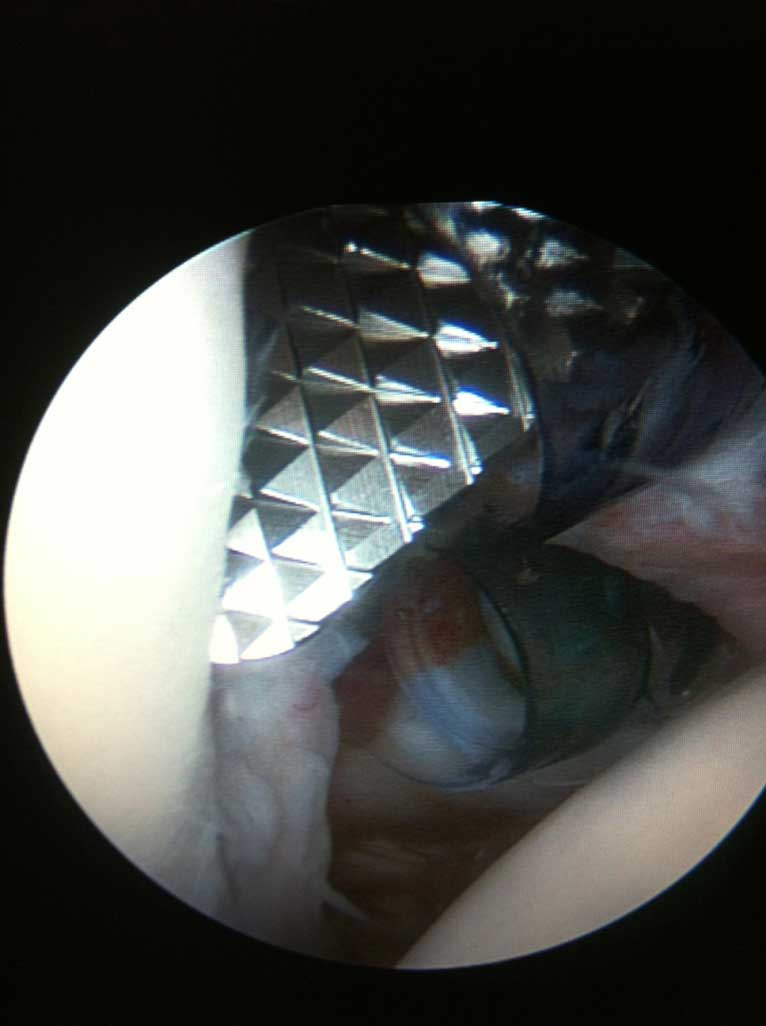

Lässt sich die Schmerzsymptomatik durch konservative entzündungshämmende Therapie nicht lindern, so wird eine arthroskopische Kalkdepotausräumung empfohlen. Dabei, innerhalb 20-30 min wird das Kalkdepot aus der Schultersehne durch 3-5 kleinen Stichinzisionen entfernt und die Sehne anschliessend genäht. Die Nachbehandlung beträgt zirka 8-10 Wochen mit Krankengymnastik und ggf. anschließender Reha Maßnahme.